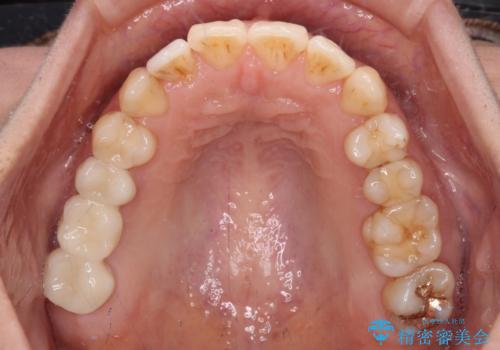

- 上下奥歯の欠損を気にして来院された患者様です。

以前矯正した後戻りにより前歯に叢生が認められたため、矯正治療の提案をしたところ、補綴治療と合わせて矯正治療を行うこととしました。

下顎欠損部はインプラントにて、上顎中間欠損部はブリッジによる補綴治療を行い、他にも気になっている銀歯をセラミックインレーやゴールドインレーにて修復治療を行うこととしました。

後戻りの程度は軽度であったため、インビザライン・ライトを用いて歯列を整えました。